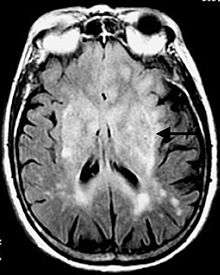

The pulse sequence is an inversion recovery technique that nulls fluids. For example, it can be used in brain imaging to suppress cerebrospinal fluid (CSF) effects on the image, so as to bring out the periventricular hyperintense lesions, such as multiple sclerosis (MS) plaques.[1]

The FLAIR sequence analysis has been especially useful in the evaluation and study of CNS disorders, involving:[2]

- Lacunar infarction

- Multiple sclerosis (MS) plaques

- Subarachnoid haemorrhage

- Head trauma

- Meningitis and other leptomeningeal diseases*

* Post-contrast FLAIR images have been added to diagnosis protocol for accurate medical assessment.[2]